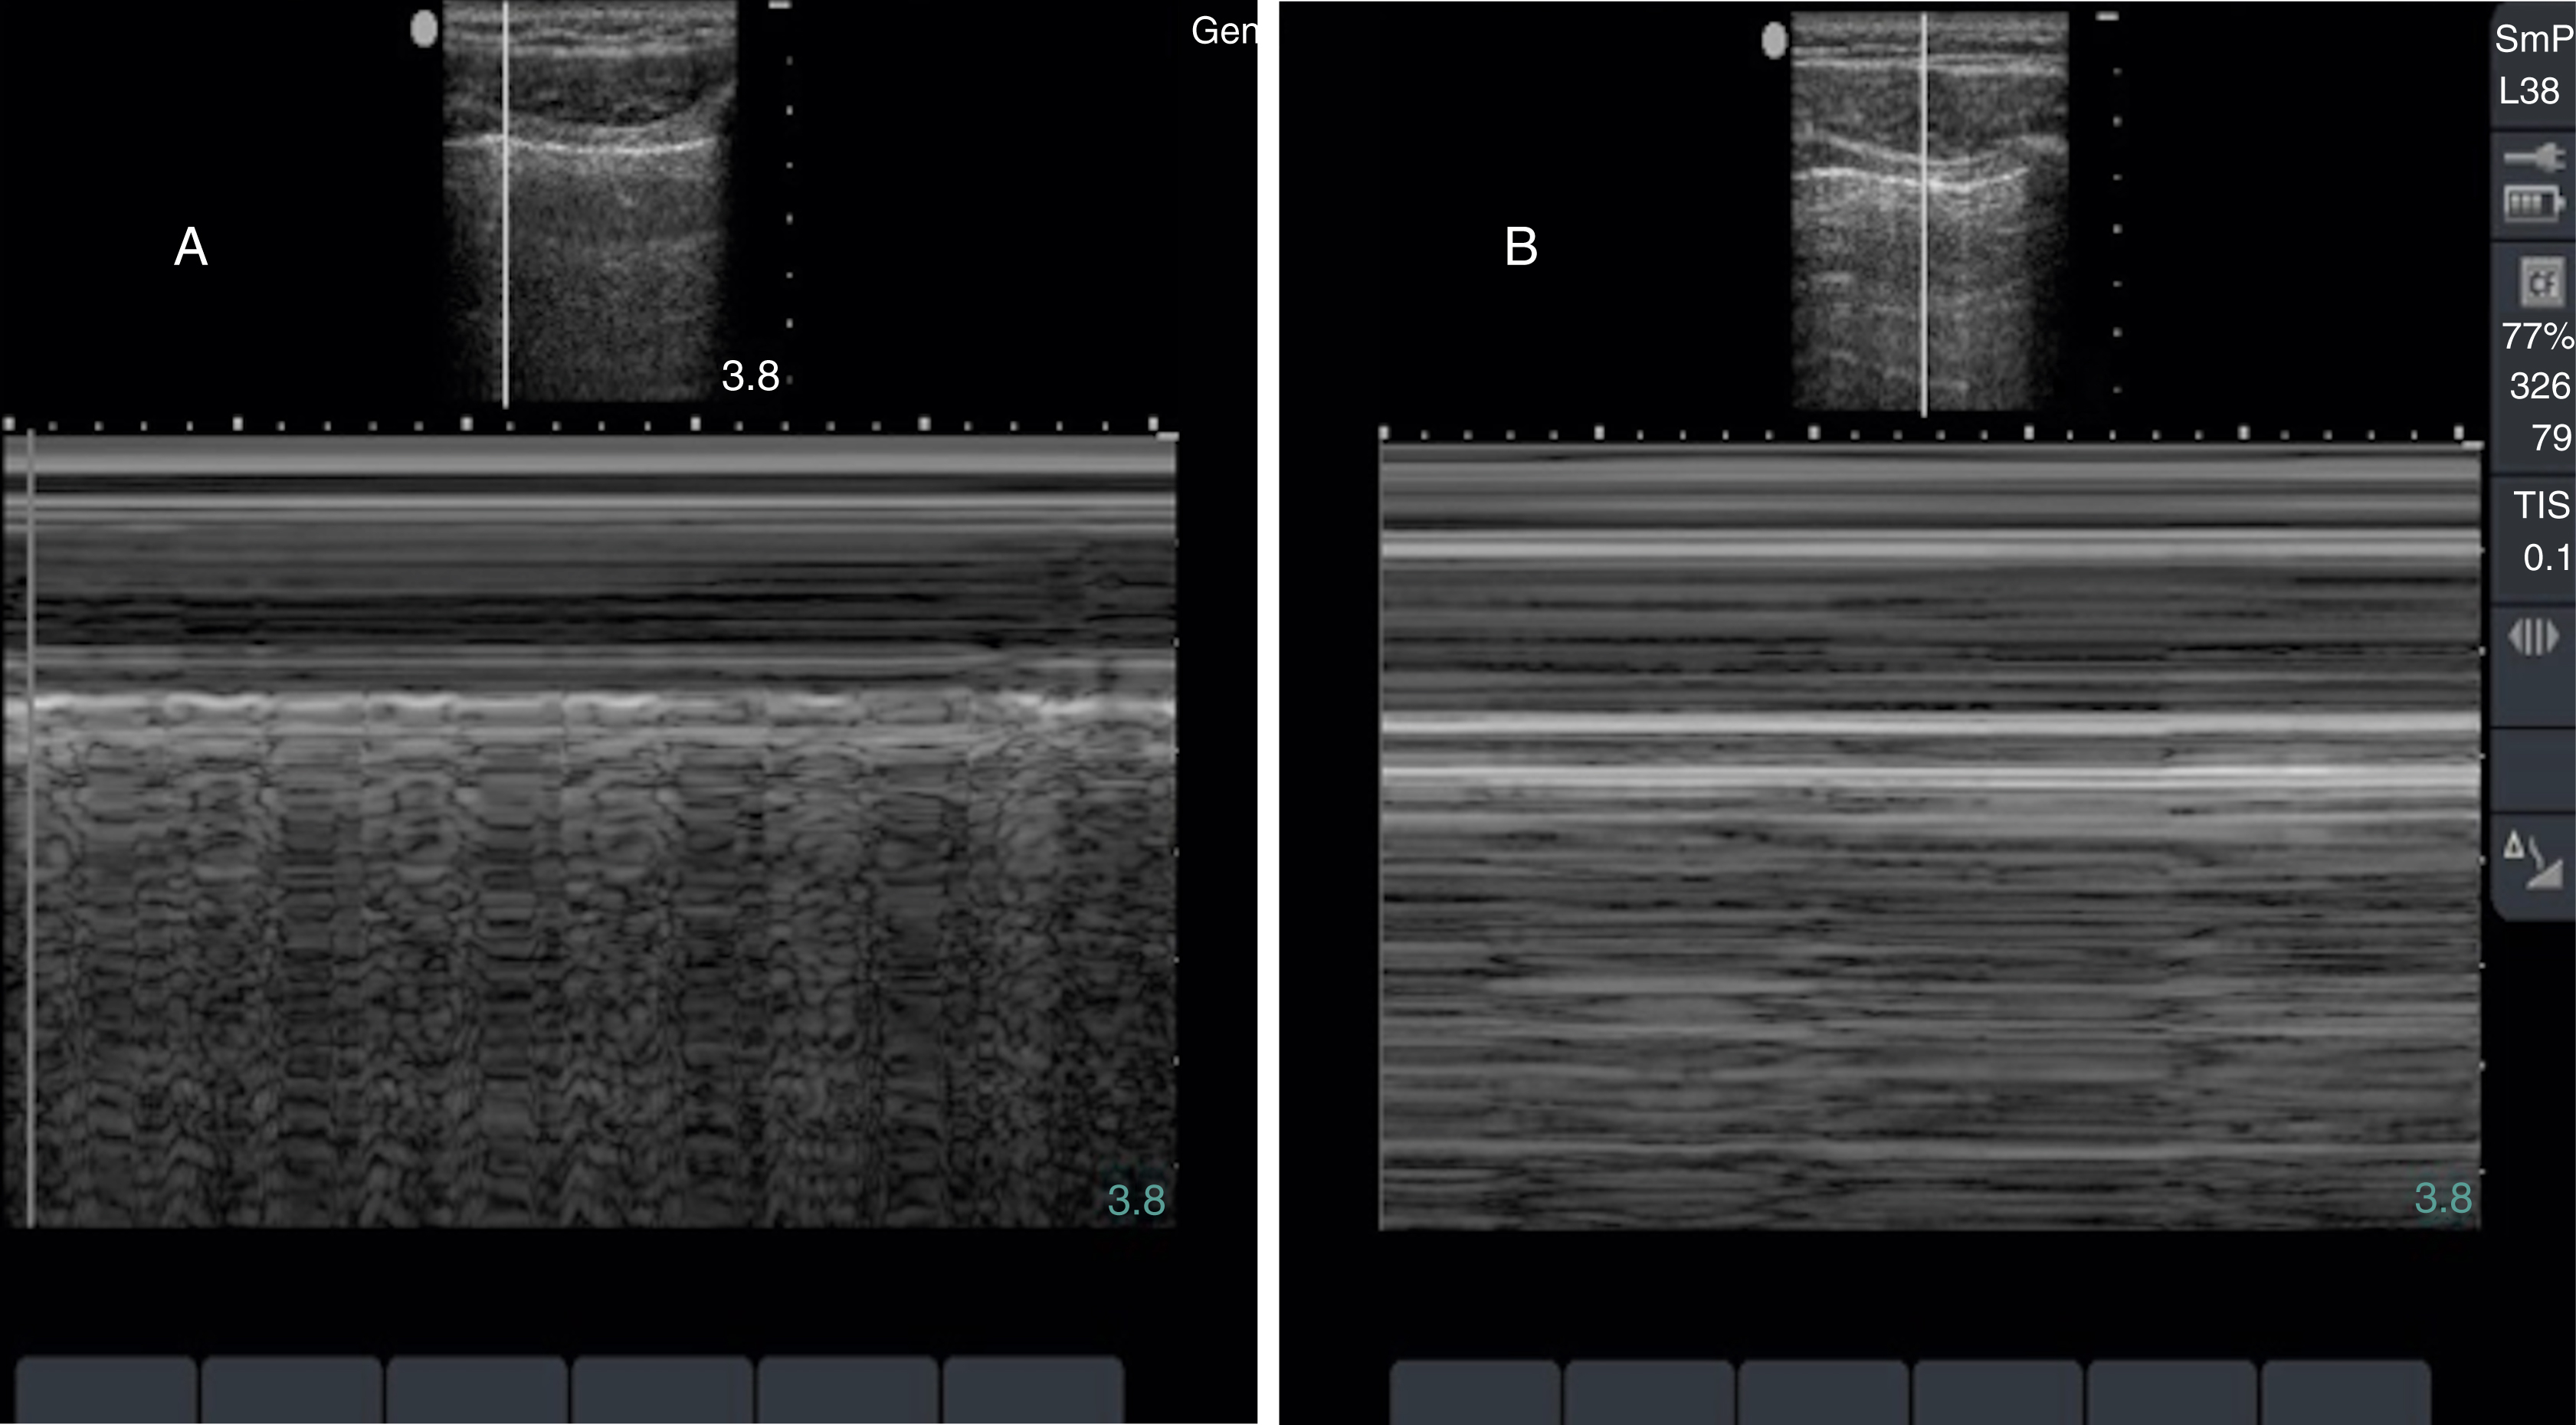

Thoracic US is often performed with a low-frequency curvilinear array or phased array transducer, although visualization of lung sliding may be enhanced, if necessary, by the use of a high-frequency linear array transducer. The original BLUE (Bedside Lung Ultrasound in Emergency) protocol evaluated 4 areas on each hemithorax, but subsequent studies have looked at a number of protocols and additional areas of the anterior, lateral, and posterior thorax. Lung sliding, a normal finding, is identified as the visceral and parietal pleura gliding against each other during normal respiration. A lines, horizontal equally spaced echogenic artifacts deep to the pleural line, are also a normal finding ( Fig. e3.14 ).

A lines signifying normal lung.

The visualization of lung sliding excludes the presence of a pneumothorax at that location on the patient’s chest wall. Although M-mode and color Doppler techniques have been described as adjuncts to the evaluation of patients with suspected pneumothorax, neither is a necessary component of the examination. Absent lung sliding can result from a variety of causes in addition to pneumothorax, including pleural adhesions or consolidations, blebs, pleurodesis, partial or complete pneumonectomy, and contralateral mainstem bronchus intubation ( Fig. e3.15 ). A lung point sign is identified at the border of the pneumothorax, where the image shows absent lung sliding until the lung moves into the interspace with respiration ( Video e3.12 ).

M mode images of the lung. (A) Normal lung with “seashore” sign. (B) Pneumothorax with “stratosphere” or “barcode” sign.